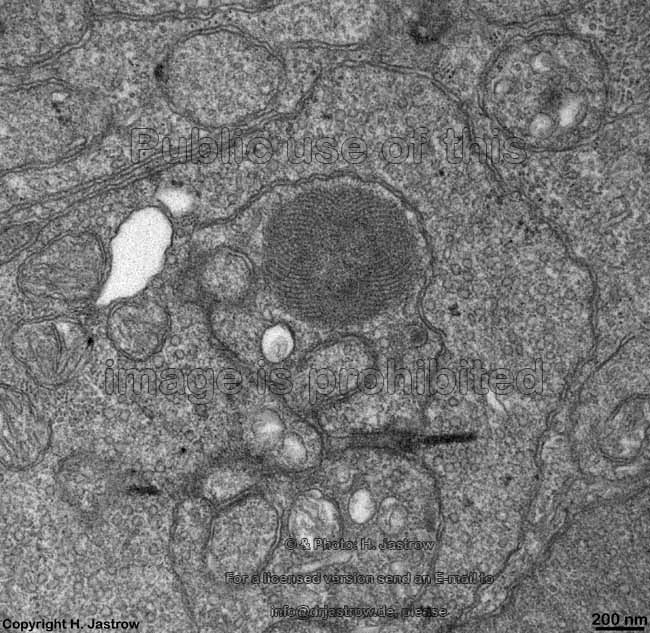

Pigment epithelium = Stratum pigmenti = Pars pigmentosa (10)

outer segments +

pigment epithelium

pigment epithelial

cell

phagocytosis of outer seg-

ments in pigment epithelium

detail thereof similar detail pigment epithelial cell

SER, cytoplasm 1

pigment epithelial cell

SER, cytoplasm 2

detail: smooth endo-

plasmic reticulum